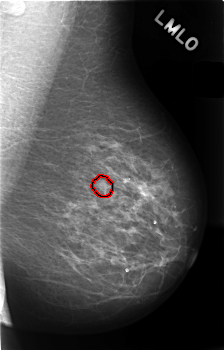

C_0408_1.LEFT_MLO

LEFT_MLO LINES 4544 PIXELS_PER_LINE 2904 BITS_PER_PIXEL 12 RESOLUTION 50 OVERLAY

FILE: C_0408_1.LEFT_MLO.OVERLAY

TOTAL_ABNORMALITIES 1

ABNORMALITY 1

LESION_TYPE CALCIFICATION TYPE AMORPHOUS DISTRIBUTION CLUSTERED

ASSESSMENT 4

SUBTLETY 1

PATHOLOGY BENIGN

TOTAL_OUTLINES 1

BOUNDARY